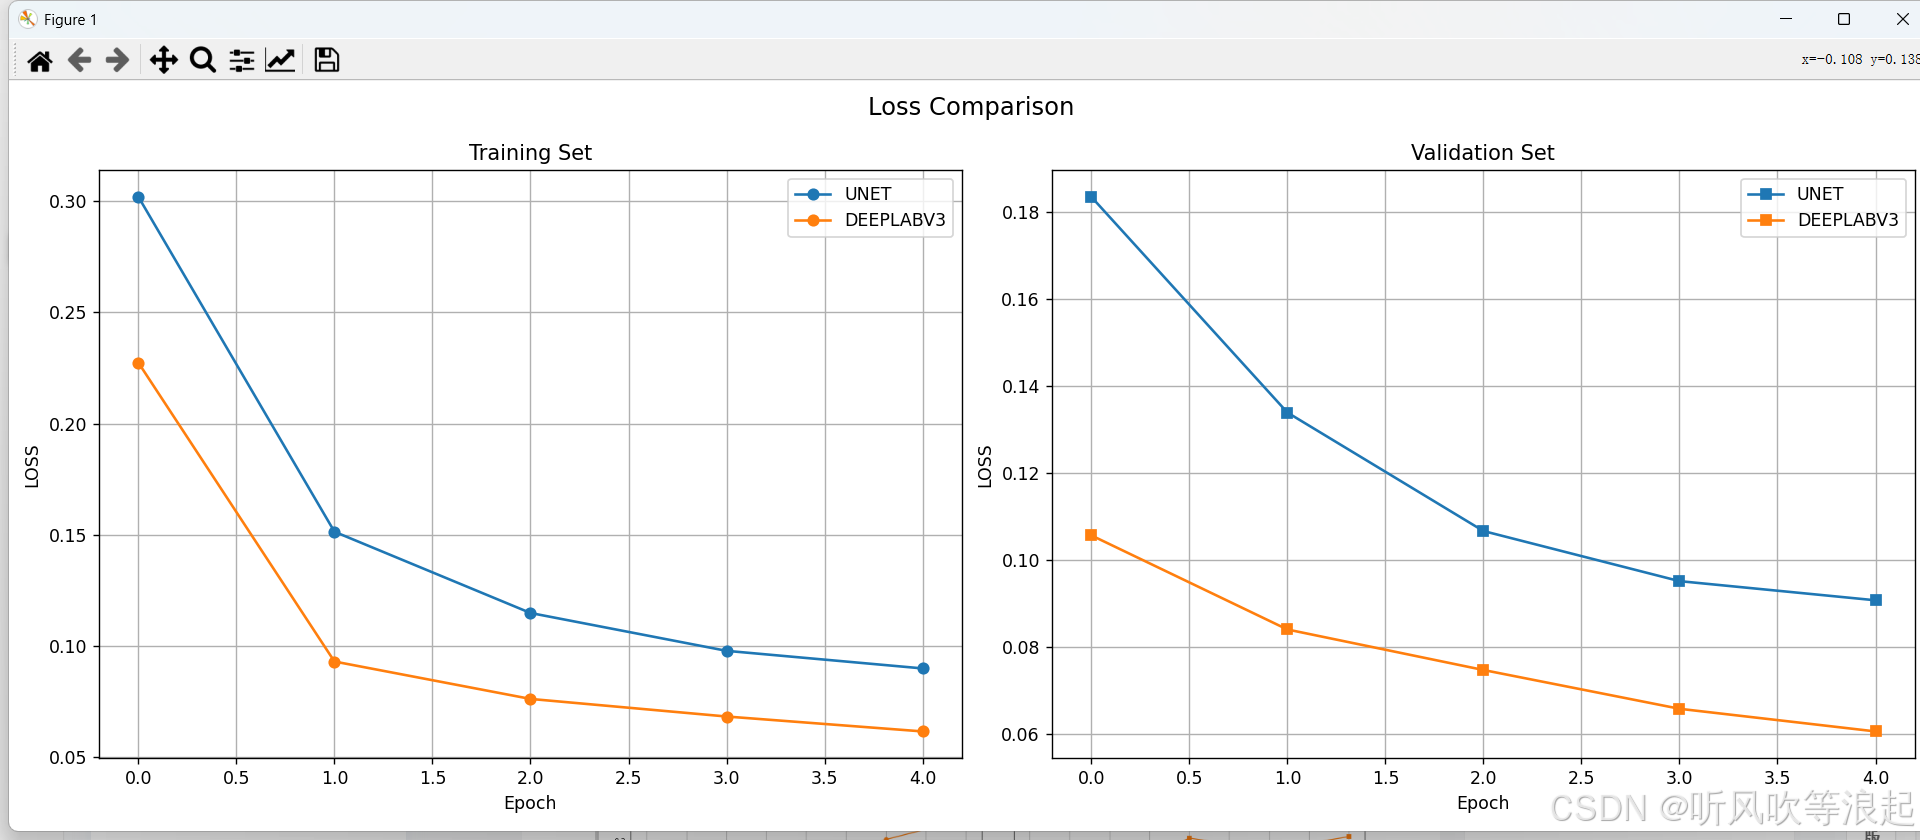

通过可视化工具可以直观比较不同模型的性能表现:

ax2.plot(epochs, values, label=model_name.upper())可视化结果通常显示:

- UNet在小数据集上通常收敛更快

- DeepLabV3在大数据集上表现更优

- 两种模型在不同指标上的曲线

这里仅仅训练了5个epoch用于测试代码的可行性,指标不做参考

3.对比